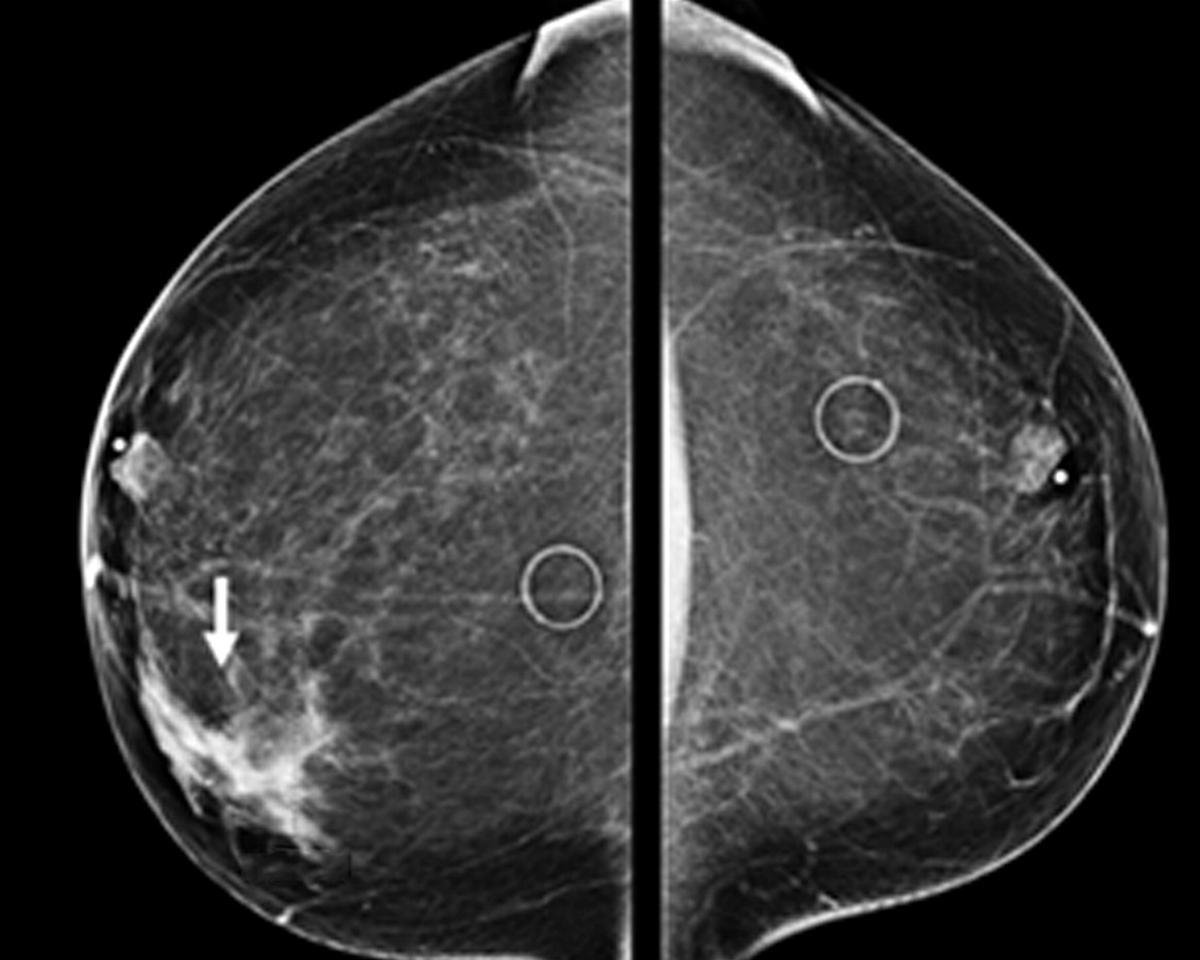

Conventional Xray Mammography It has become widely acceptable method for screening of women after certain age for early detection of malignant and pre malignant conditions of breast.

Conventional Xray Mammography It has become widely acceptable method for screening of women after certain age for early detection of malignant and pre malignant conditions of breast.